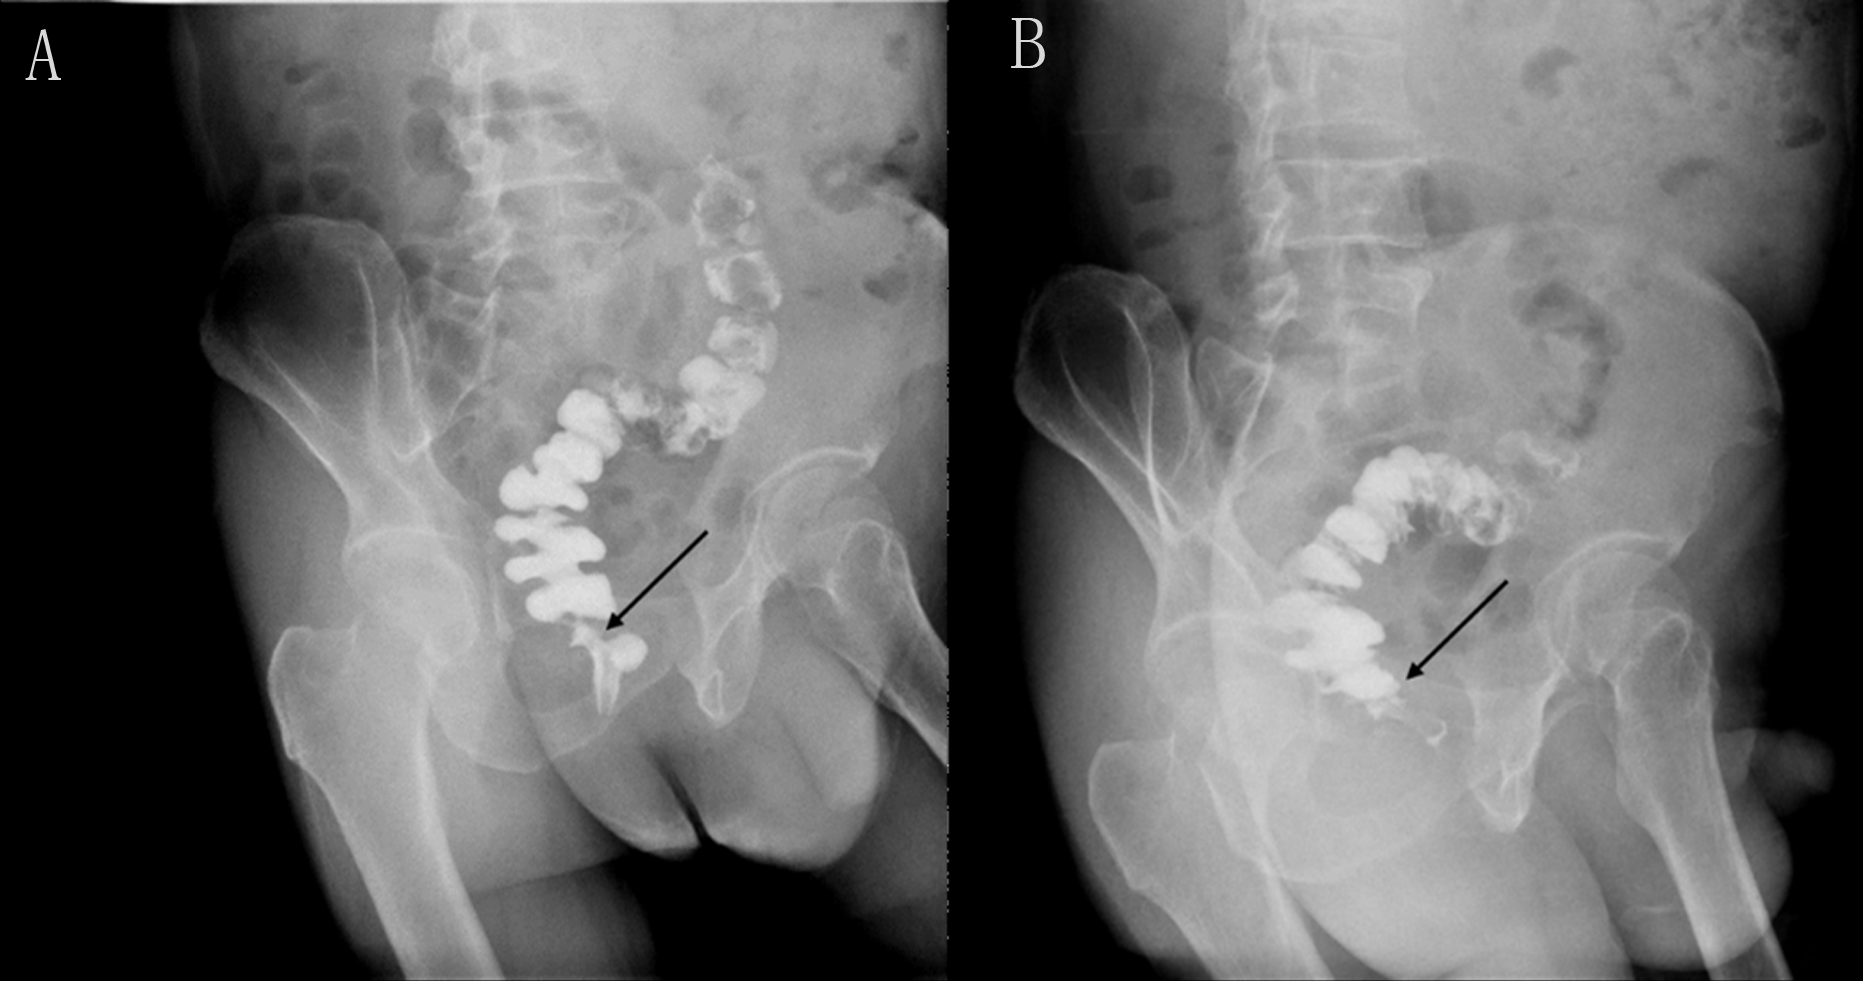

Seeking further treatment, he approached our team. Pelvic floor electromyography revealed mild spasm of the puborectal muscle, with no significant abnormalities in the static tension or contraction strength of the anal sphincter muscles. This indicated that pelvic floor muscle dysfunction was not the primary cause of his difficulty in defecation. Meanwhile, rectal radiography also showed no evidence of anastomotic stricture (Figure 2). Upon digital rectal examination, it was found that the index finger passed readily, but the anastomotic ring was noted to be inelastic. Based on these findings, we hypothesized that although the anastomosis was large enough by traditional AS standards, it may have failed to functionally relax and expand during defecation, thus contributing to the difficulty in bowel movements. Therefore, we recommended instrumental anal dilatation due to its wide range of diameter and ease of operation. Hegar’s dilatation was initiated at 1.5 cm and gradually increased to 2.2 cm (Figure 3) until the patient felt discomfort. On the first day post-treatment, his symptoms significantly improved. However, recurrence occurred 2 days later. Therefore, the patient was advised to undergo Hegar’s dilatation every alternate day for 1 week, twice a week for another week, and once a week for the following 2 weeks. Subsequently, the patient experienced smoother voluntary defecation without the need for laxatives in the subsequent 6 months. We continue to monitor the patient closely at our outpatient department. The timeline of patient care and key interventions is provided in Supplementary Table S1.

Figure 2

www.frontiersin.org

Figure 2 Rectal iodine contrast examination revealed no rectal anastomotic stricture. (A) Supine position. (B) Left lateral position. The arrow indicates the location of the anastomosis, which is wider than 1.2 cm.